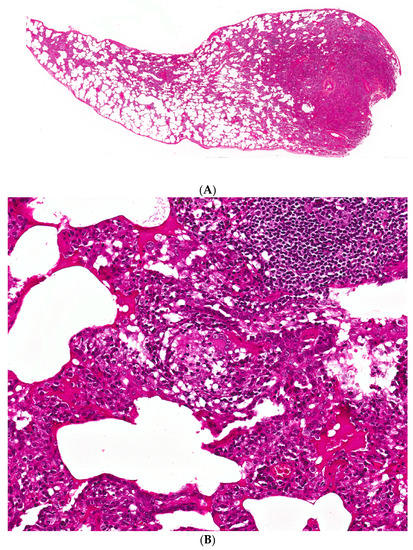

Figure 2. (A) A case of hypersensitivity pneumonitis shows peribronchiolar chronic inflammation of varying intensity around bronchovascular bundles. (B) A single, small, poorly-formed granuloma is found within the interstitium

The primary histopathological features considered characteristic of subacute HP include the triad of cellular bronchiolitis, lymphoplasmacytic interstitial infiltrates, and non-necrotizing granulomas (Figure 2) [47]. The inflammation is composed mainly of lymphocytes in a bronchiolocentric distribution. Proliferative bronchiolitis obliterans has been described in patients with farmer’s lung, while constrictive bronchiolitis has been reported in pigeon breeder’s disease [48,49]. The granulomas are small in size and not as well-formed as those seen in sarcoidosis. Multinucleated giant cells may be present as constituents of granulomas and/or also be present singly, not infrequently containing cholesterol clefts. It should be noted that granulomatous features may be absent in almost one third of surgical lung biopsies from patients with fibrotic HP [50]. Most granulomas are identifiable on routine staining, although cathepsin K, a protease expressed in activated macrophages, may be of additional value. However, it is not specific for HP granulomas [51]. Finally, occasional areas of organizing pneumonia with Masson bodies are often seen in subacute damage, while peribronchial lymphoid hyperplasia is frequently evident [50].